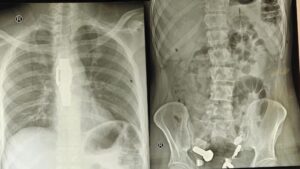

แพทย์ที่ทำการตรวจพบความผิดปกติจากผลเอกซเรย์ ซึ่งแสดงให้เห็นว่า มีนาฬิกาข้อมือติดอยู่ในหลอดอาหาร ขณะที่ในลำไส้ใหญ่พบเศษเหล็กและชิ้นส่วนโลหะต่าง ๆ เช่น น็อต สลักเกลียว และสกรู อัดแน่นสะสมอยู่เต็มไปหมด